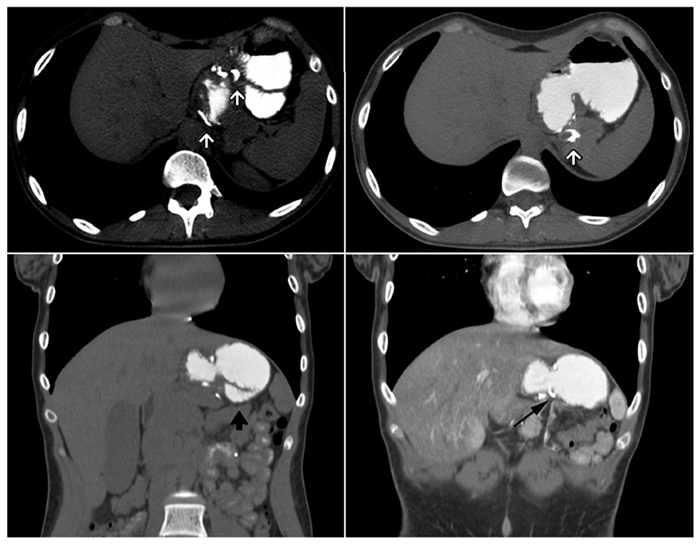

El esófago se encuentra dilatado en toda su extensión con el contenido de contraste hasta su tercio superior. Se observa una laceración esofágica en la cara anterior, en su tercio inferior, a 65 mm de la unión gastroesofágica (Figura 2). Se identifica abundante contenido de material de contraste en la cámara gástrica, asociado a las suturas mecánicas a su alrededor y una distensión del asa anastomosada, observando una oclusión intestinal del asa aferente (Figura 3).

La paciente fue sometida a una cirugía donde se identificó un gran proceso inflamatorio a nivel del asa alimentaria en la zona de la anastomosis gastroyeyunal. Se reconoció el bypass anillado con un deslizamiento del asa alimentaria (Figura 3). Al liberar el remanente gástrico se observó una fístula gastroesofágica. Se decidió resecar el extremo inferior del pouch y los primeros 10 cm del asa alimentaria para luego realizar una nueva anastomosis gastroyeyunal. Se optó por un tratamiento conservador de la perforación dado su pequeño tamaño. Luego del acto quirúrgico, permaneció internada para control clínico, evolucionando favorablemente, por lo que fue dada de alta con un posterior seguimiento de forma ambulatoria por el servicio de cirugía general.